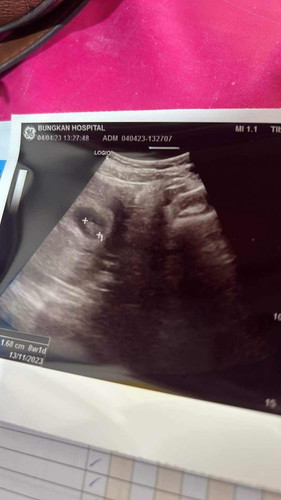

8สัปดาห์เจอน้องแล้ว

ของแม่ๆเจอนอนตอน8w มั้ยคะ วันนี้ไปฝากครรภ์ครั้งแรก คุณหมออัลตราซาวด์ เจอน้องดีใจตื้นตันมาก

เจอ8wหัวใจดวงน้อยด้วย🥰